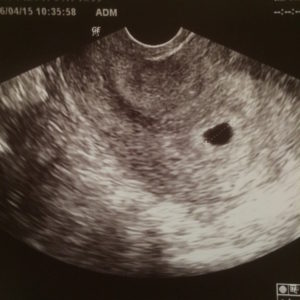

定期検診で、当初黒豆のようだった彼は

BLACK BEANS、略してB.Bと呼ばれ、

その後ある程度カタチになり始めたら

両手を上げていたのでPUT YOUR HANDS UPを略し

暫定的に今、プッくんと呼ばれている。

(B.B時代)